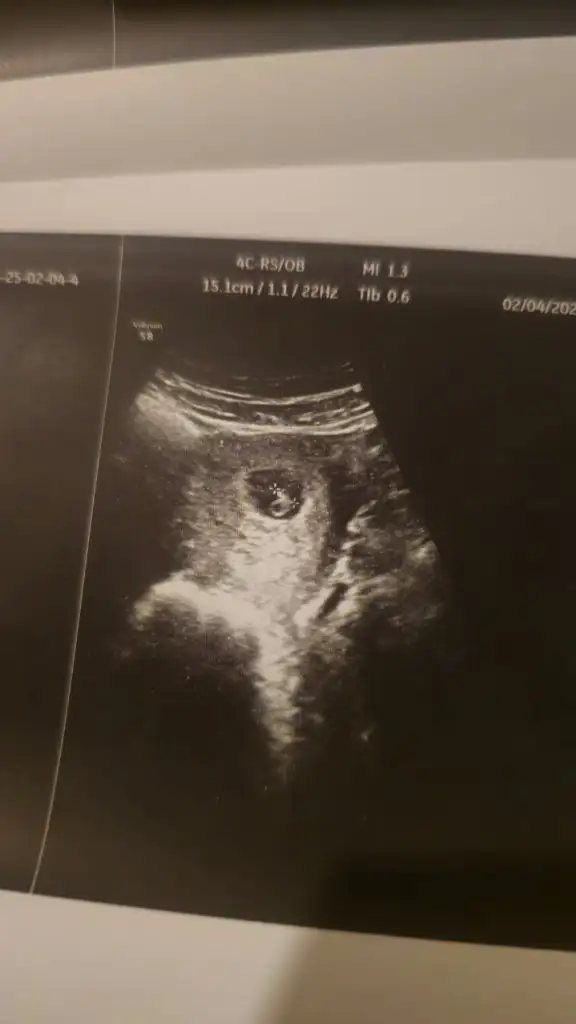

Şuan tam 7 hafta 5 günlük

Boş keseyi 25 Ocakta gördük

Kalp sesini 4 Şubatta duyduk🥰